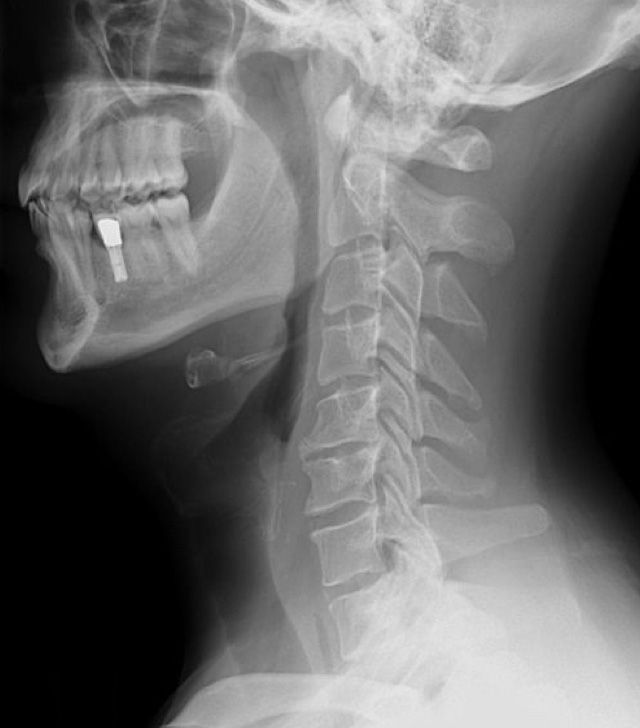

Phase II Cervical Spine

Bone spurs and abnormal bony growths distort the shape and function of the vertebrae.

Recognized by the X-ray views of the spine by visible bone spurs and rough edges of the vertebrae. Soft tissues, such as discs & Ligaments degenerate from the lack of normal joint movement. Again, pain or other symptoms may not be present.